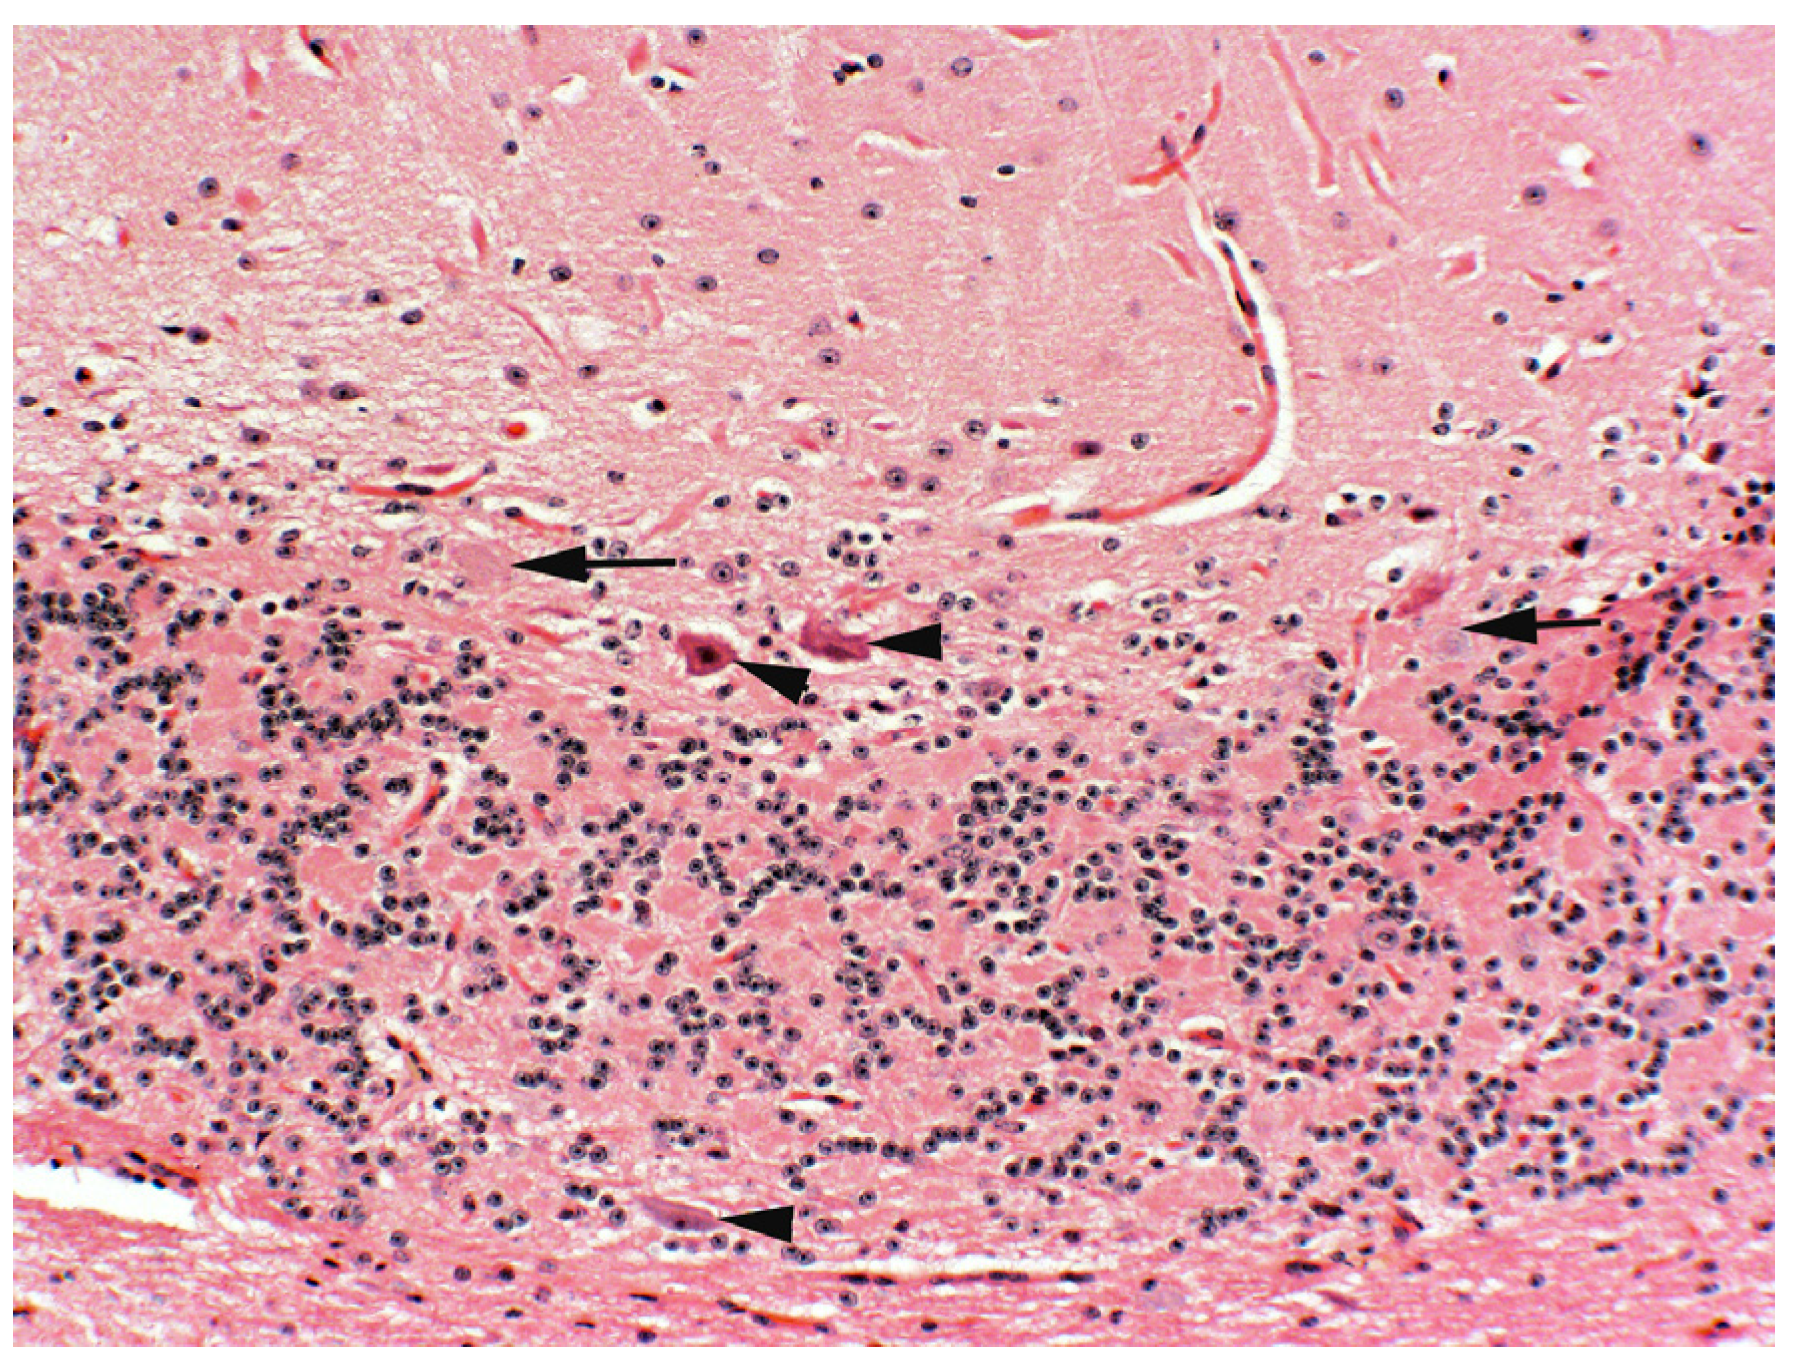

Histologic changes in the positive control wethers included vacuolation, eosinophilic swelling, pyknosis, and necrosis of neurons in the cerebellum, especially cerebellar Purkinje cells (Figure 2A), basal ganglia, hypothalamus, medulla and ventral horns of the spinal cord. Dystrophic axons (spheroids) were present in the white tracts of the cerebellar peduncles and white tracts of the medulla. Vacuolation in visceral tissues resolved with minimal vacuolation of the exocrine pancreas. Sheep that were dosed with durations of 9 and 15 days had less severe Purkinje cell vacuolation (Figure 2B) with minimal neuronal pyknosis and no obvious axonal dystrophy. Animals dosed at durations of 5 days or less (with both 7- and 14-day recovery periods) and the negative controls had no or minimal Purkinje cell vacuolation (Figure 2C,D). Furthermore, no neuronal pyknosis and axonal dystrophy were observed in these lambs.

Figure 2.

Photomicrograph of central lobe of the cerebellum of locoweed-poisoned sheep with varying dosing durations with a total of 45 total dosing days. (A)—lamb dosed continuously with locoweed for 45 days with no recovery periods. Notice the marked, fine, granular vacuolation in Purkinje cells (arrows). Small numbers of pyknotic Purkinje cells were observed. (B)—lamb similarly dosed for 45 days with durations of 15 days (3 courses) each followed by a 14-day recovery period. Notice the Purkinje cells have similar but less severe fine granular vacuolation (arrows). No pyknotic neurons were identified. (C)—Lamb similarly dosed with locoweed for 45 days with durations of 5 days (9 courses) each followed by a 14-day recovery period. Notice the minimal but real fine granular cytoplasmic vacuolation (arrow). No pyknotic neurons were identified. (D)—Negative control lambs that were similarly dosed via oral gavage with ground alfalfa for 45 days. Notice the absence of Purkinje cell change. Similarly, no pyknotic neurons were identified.

Locoweed-induced permanent lesions include neuronal swelling and vacuolation followed by severe vacuolation, chromatolysis and esosinophilia, pyknosis and necrosis [10,11]. In this study, lambs dosed at durations of 5 days with 7- and 14-day recovery periods had neuronal changes that were less severe and more likely to resolve. Shorter durations did not have neuronal changes. This indicates that lambs exposed to locoweed for durations of 5 days or less with 7-day withdrawal periods are not likely to develop permanent locoweed-induced neurologic disease.

Previous dose-response studies using sheep and cattle suggest that cattle are likely to have similar responses to intermittent poisoning [8]. Studies also suggest that higher doses do not result in additional or more severe lesions [10,12]. Intermittent locoweed exposure often naturally occurs in locoweed endemic areas. These animals are often moved between different ranges, making it less likely for livestock to be exposed to locoweed for durations of longer than 45 to 60 days. Such intermittent poisoning tends to be followed by 9 or 10 months of recovery. This seasonal locoweed poisoning eventually results in permanent neuronal damage. After several seasons, such repeatedly poisoned animals have reduced numbers of cerebellar Purkinje cells (Figure 3). Microscopically, this change is best assessed in the central cerebellar lobe. Affected cattle lose condition. Though they may recover reproductive function, they will have decreased ability to move, forage and lactate. This results in small, long-haired calves that take a long time to finish. The affected cows often have behavioral changes, including becoming aggressive and difficult to handle. If intermittent poisoning is used, monitoring animals for such cumulative changes will be helpful in assessing management and optimizing frequency, duration and clearance periods.

Figure 3.

Photomicrograph of cerebellar Purkinje cells from a cow that was previously poisoned by Green river milkvetch (Astragalus pubentissimus) for at least 5 years. Before necropsy, she was thin, wasted, and anxious and aggressive to handlers. Her 6-month-old calf was small (about 150 kg or 30% smaller than her herdmates) with long hair. Notice the paucity of cerebellar Purkinje cells in the central cerebellar lobe (arrows indicate empty baskets in locations of missing Purkinje cells). The arrow heads are degenerative pyknotic Purkinje cells. The cerebellar crus and white tracts in the medulla contained numerous axonal spheroids (not shown).